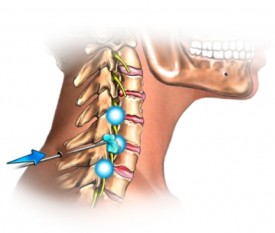

Vertebrogenous (цервикален) радикулит

Маточната шийка радикулит придружен от едностранна болка в областта на шията, по-лошо, когато се движат главата, което често се простира до гръдни и тилната област.

Влошаване обикновено се появява след сън в неудобно положение, или на висока възглавница, както и във връзка с физическо или психическо пренапрежение, хипотермия, настинки.

Болезнената синдром се изразява умерено.